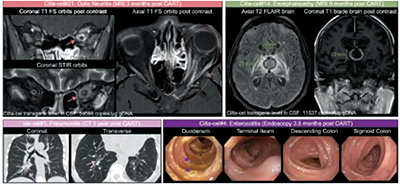

靶向B细胞成熟抗原(BCMA)的CAR T细胞疗法革新了MM的治疗,但也可能引发独特的毒性作用,包括脑神经麻痹、帕金森综合征和肠结炎,这些被统称为CirAE。

在西达基奥仑赛治疗者中,最常见的CirAE为脑神经麻痹(8%)、肠炎(5.6%)、帕金森病(4.8%)和关节炎(1.6%),而迟发性免疫效应细胞相关神经毒性综合征(ICANS)、脑病变和周围神经病变则较少见(各0.8%)。2例患者在西达基奥仑赛治疗下出现多次CirAE,其中1例74岁男性患者发生3例次不同的CirAE。ide-cel治疗中唯一被观察到的CirAE为肺炎。